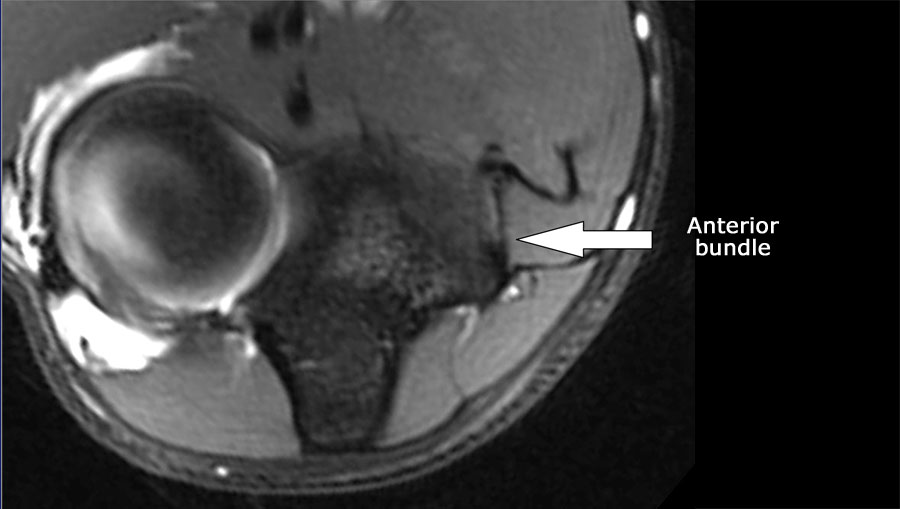

Luôn sử dụng hình ảnh mặt cắt ngang (axial) khi nghiên cứu các dây chằng, đặc biệt là dây chằng bên trụ (UCL).

Scroll through the images.

- Nếu bạn nhìn vào mỏm trên lồi cầu trong, bạn sẽ nhận thấy bó sau như một cấu trúc mỏng (mũi tên xanh).

- Lưu ý rằng bó trước dày hơn nhiều (mũi tên trắng).

- Bạn có thể thấy sự khác biệt giữa dây chằng trước và dây chằng sau mặc dù chúng tạo thành một dây chằng duy nhất.

- Khi đi về phía xa, chúng ta sẽ thấy chúng hợp nhất lại để bám vào củ sublime.